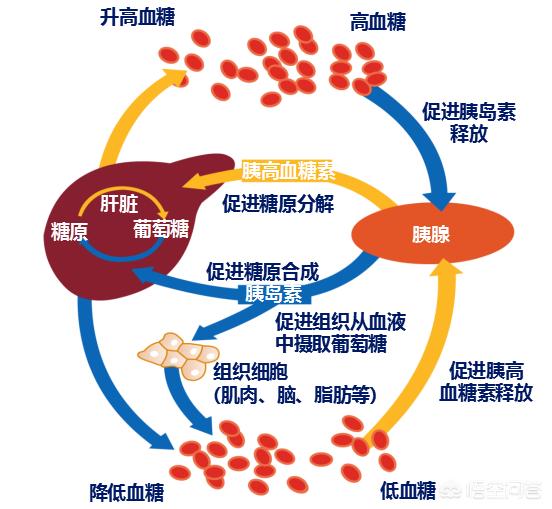

健常人の血中インスリンの増減は血糖値とほぼ同期しており、食後に血糖値が上がるとインスリンの分泌が直ちに増加して血糖値を正常範囲に戻し、血糖値が下がるとインスリンの分泌も直ちに減少して低血糖を起こさない。

糖尿病の前段階(糖尿病になる直前)、または糖尿病の初期段階では、インスリンの分泌量が大幅に減少していないが、分泌が遅くなり始め、血糖値と同期していない、血糖値が食後に上昇し、インスリンの分泌が出てこない、その結果、血糖値が高すぎる上昇;次の食事の血糖値が下がってくる、ピークではなく、インスリンの分泌は、食前の空腹感によって引き起こされる低血糖になります。